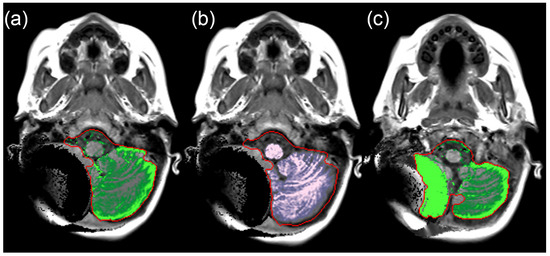

2.3. Manual Volume Measurements